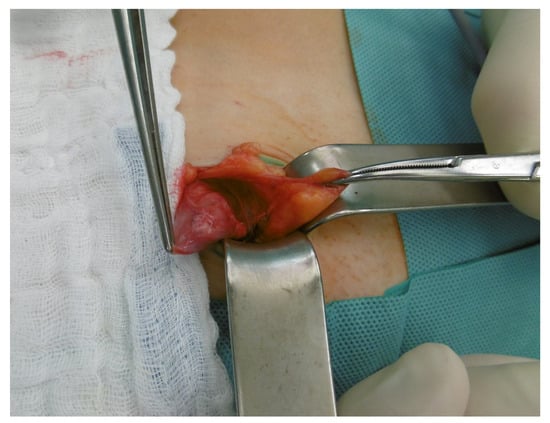

3. Case Report